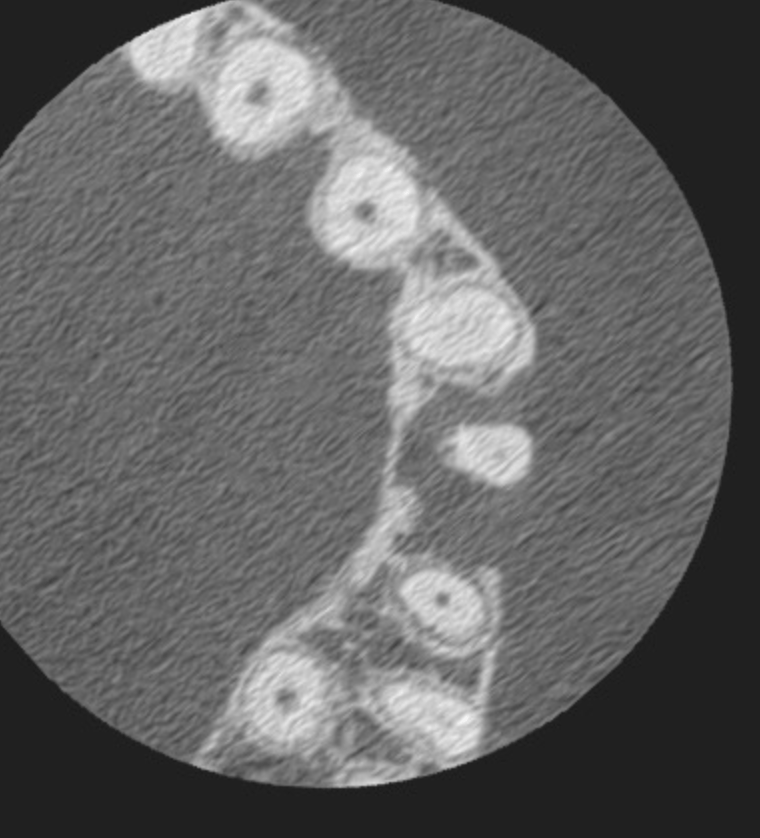

Vertical root fracture